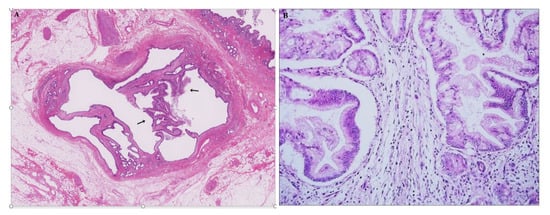

2.2.1. Cross Sectional Imaging

- Aslam, A.; Wasnik, A.P.; Shi, J.; Sahai, V.; Mendiratta-Lala, M. Intraductal papillary neoplasm of the bile duct (IPNB): CT and MRI appearance with radiology-pathology correlation. Clin. Imaging 2020, 66, 10–17. [Google Scholar] [CrossRef]

- Katabathina, V.S.; Flaherty, E.M.; Dasyam, A.K.; Menias, C.O.; Riddle, N.D.; Lath, N.; Kozaka, K.; Matsui, O.; Nakanuma, Y.; Prasad, S.R. “Biliary diseases with pancreatic counterparts”: Cross-sectional imaging findings. Radiographics 2016, 36, 374–392. [Google Scholar] [CrossRef]

- Park, H.J.; Kim, S.Y.; Kim, H.J.; Lee, S.S.; Hong, G.S.; Byun, J.H.; Hong, S.M.; Lee, M.G. Intraductal papillary neoplasm of the bile duct: Clinical, imaging, and pathologic features. Am. J. Roentgenol. 2018, 211, 67–75. [Google Scholar] [CrossRef]